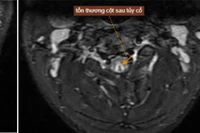

Hình ảnh tổn thương tủy sống trên bệnh nhân ngộ độc khí N2O.

Vợ anh, chị H. cũng xuất hiện triệu chứng tương tự: Tê bì hai bàn chân, cảm giác “như kiến bò trong người”, đi lại loạng choạng. Đến khi vào Trung tâm Chống độc, bác sĩ kết luận cả hai tổn thương tủy sống cổ do ngộ độc khí N₂O, ảnh hưởng đến dây thần kinh vận động và cảm giác.

Có bệnh nhân chỉ mới 20 tuổi, sau vài tháng dùng bóng cười đã phải nhập viện vì liệt tứ chi. Chụp MRI cho thấy tổn thương tủy sống không thể hồi phục.